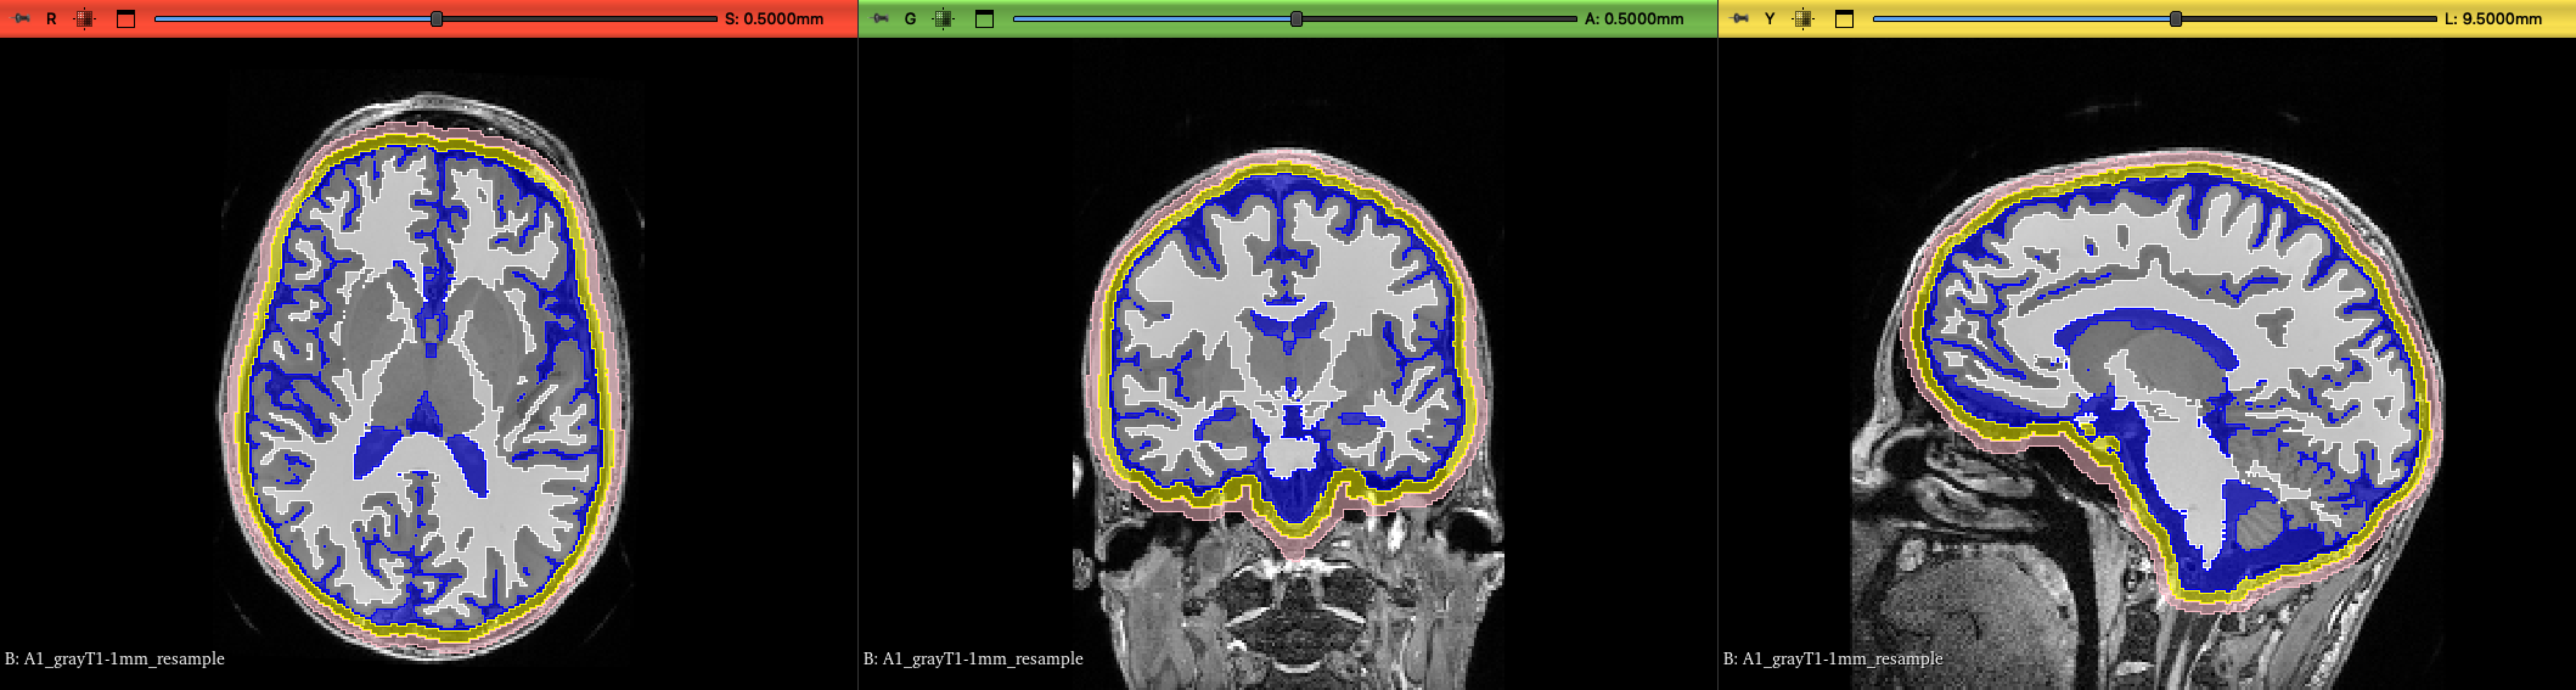

We present results similarly shown in our preliminary work [58]. This includes computed potentials overlaid onto both the labelled FE mesh and the volumetric MRI images with the SPL/NAC brain atlas label map. We projected electrodes onto the scalp surface following the international standard 10-20 electrode system [64] using open-source 3D Slicer extension, GeodesicSlicer [65], and evaluated the potentials at these locations.

Furthermore, we demonstrate the capability to overlay computed potentials onto MRI scans and the OAP’s SPL/NAC brain atlas label map. This feature may prove particularly useful for medical professionals in clinical settings, enabling them to correlate simulated electrical activity with anatomical structures more easily.

Refer to caption

Figure 13: Electric potential in the brain generated by a current dipole located at the left middle temporal gyrus overlaid onto the volumetric images in the axial, coronal and sagittal planes. Top row: Overlaid onto T-1 weighted MRI scan. Bottom row: Overlaid onto the OAP’s SPL/NAC brain atlas label maps.